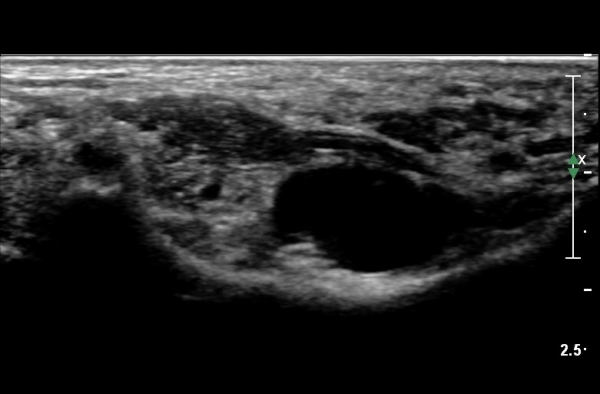

ŽÃËÀÚ¸¦ Á¶±Ý ¸»´ÜÀ¸·Î À̵¿ÇÏ´Ï Èİæ°ñ½Å°æÀÌ ³»ÃøÁ·Àú½Å°æ°ú ¿ÜÃøÁ·Àú½Å°æÀ¸·Î ºÐÁöÇÑ´Ù(»çÁø 2).